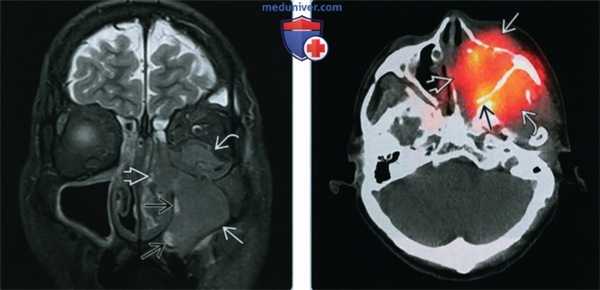

(Слева) При корональной МРТ Т2 FS определяется гипоинтенсивное мягкотканное образование, заполняющее левую верхнечелюстную пазуху и распространяющееся в полость носа слева и орбиту. Обратите внимание на гиперинтенсивный «запертый» секрет во внутренних отделах левой верхнечелюстной пазухи.

(Справа) При аксиальной ОФЭКТ/КТ с пентетреотидом (индий-111) у этого же пациента определяется повышенное накопление радиоактивной метки в СННР левой верхнечелюстной пазухи. Опухоль распространяется в предчелюстные мягкие ткани слева, полость носа, жировую клетчатку позади верхней челюсти, и крылонебную ямку.

2. КТ при синоназальном нейроэндокринном раке:

• КТ с КУ:

о Мягкотканная опухоль с вариабельным контрастированием, нечеткими краями и инвазией окружающих структур

• «Костная» КТ:

о Агрессивная деструкция костей

3. МРТ при синоназальном нейроэндокринном раке:

• Т1 ВИ:

о Плохо отграниченное мягкотканное образование, изоинтенсивное мышцам

• STIR:

о Неоднородный, гипоинтенсивный или промежуточный длительный TR сигнал

• T1 BИ C+ FS:

о Вариабельное, обычно диффузное контрастирование

4. Сцинтиграфия:

• Сцинтиграфия с пентетреотидом (индий-111):

о ↑ накопление в высоко и умеренно дифференцированном СНЭР

5. Рекомендации по визуализации:

• Лучший метод визуализации:

о Мультипланарная MPT С+ (гадолиний) с жироподавлением лучше всего для определения границ опухоли